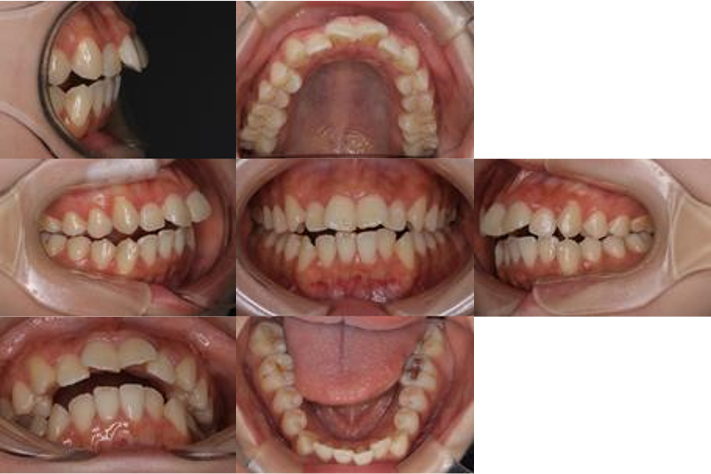

開咬を主訴に来院されました。診断したところ、改善点が大きく4つに分けられます。

①出っ歯の部分(オーバージェット)

「ジェット」とは、上の前歯が下の前歯よりもどれくらい前方に突き出ているかという「前後の距離」のことです。いわゆる「出っ歯」の状態が強いということです。開咬(上下の隙間)だけでなく、前後にも距離があるため、前歯を後ろに下げながら、かつ下に降ろして噛み合わせるという「二次元的な移動」が必要になり、治療の難易度が上がります。

②前歯の開咬

これは文字通り、前歯が噛み合わずに隙間が開いている状態です。奥歯は当たっているのに、前歯(中切歯・側切歯)が上下でスカスカに空いていることです。隙間が何ミリあるかによって、インビザラインで「歯をどれだけ垂直に伸ばす(圧下・挺出)」必要があるかを判断します。重度の場合は、骨格の問題も疑われます。

③犬歯関係 II級(けんしかんけい にきゅう)

「犬歯(けんし)」は、前から3番目の尖った歯のことで、ここの噛み合わせのズレを指しています。「下の犬歯に対して、上の犬歯が本来の位置より前に出ている」状態をII級と呼びます。犬歯は噛み合わせの肝心な歯です。ここがII級だと、全体の歯車がズレている状態なので、前歯だけを閉じても根本解決になりません。奥歯全体を後ろに下げる(遠心移動)などの治療が必要になることが多いです。

④前歯の捻転(ねんてん)

「捻転(ねんてん)」とは、歯が本来の向きから回転して(ねじれて)生えていることです。前歯が斜めを向いていたり、横を向いている状態です。インビザライン(マウスピース)は、実は歯を「回転させる」動きが少し苦手です。ねじれた歯を真っ直ぐに直してから隙間を閉じないと、見た目の美しさが半減してしまいます。